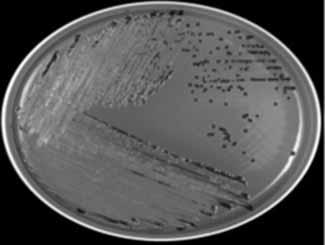

Tulemused mikrobioloogia valdkonnas. Mikrobioloogia alal on seni valminud kolm õppetöös kasutatavat juhendit: „Uriini mikrobioloogilise analüüsi juhend …“ (2017), autor H. Sepp; „Juhend Salmonella spp. isoleerimiseks ja samastamiseks kliinilisest materjalist“ (2018), autor M. Stepanenkova, (joonis 4); „Staphylococcus spp. samastamise juhend …“ (2018), autor C. Platonova.

ARTIKLID RAKENDUSUURINGUTEST a. b.

c. d.

Joonis 4. Fotod Marina Stepanenkova juhendist Salmonella spp. isoleerimisest ja samastamisest; a) rohelisel Hektoen söötmel olevad mustjad Salmonella spp. kolooniad, b) punasel XLD söötmel on sama bakteri mustjad kolooniad, c) roosal MacConkey söötmel on valkjas-hallikad kolooniad, d) on näha API 20E testi näidis, kus viaalides olev lahus on muutnud oma värvi